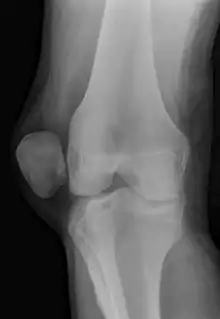

| X-ray showing a patellar dislocation, with the patella out to the side. | |